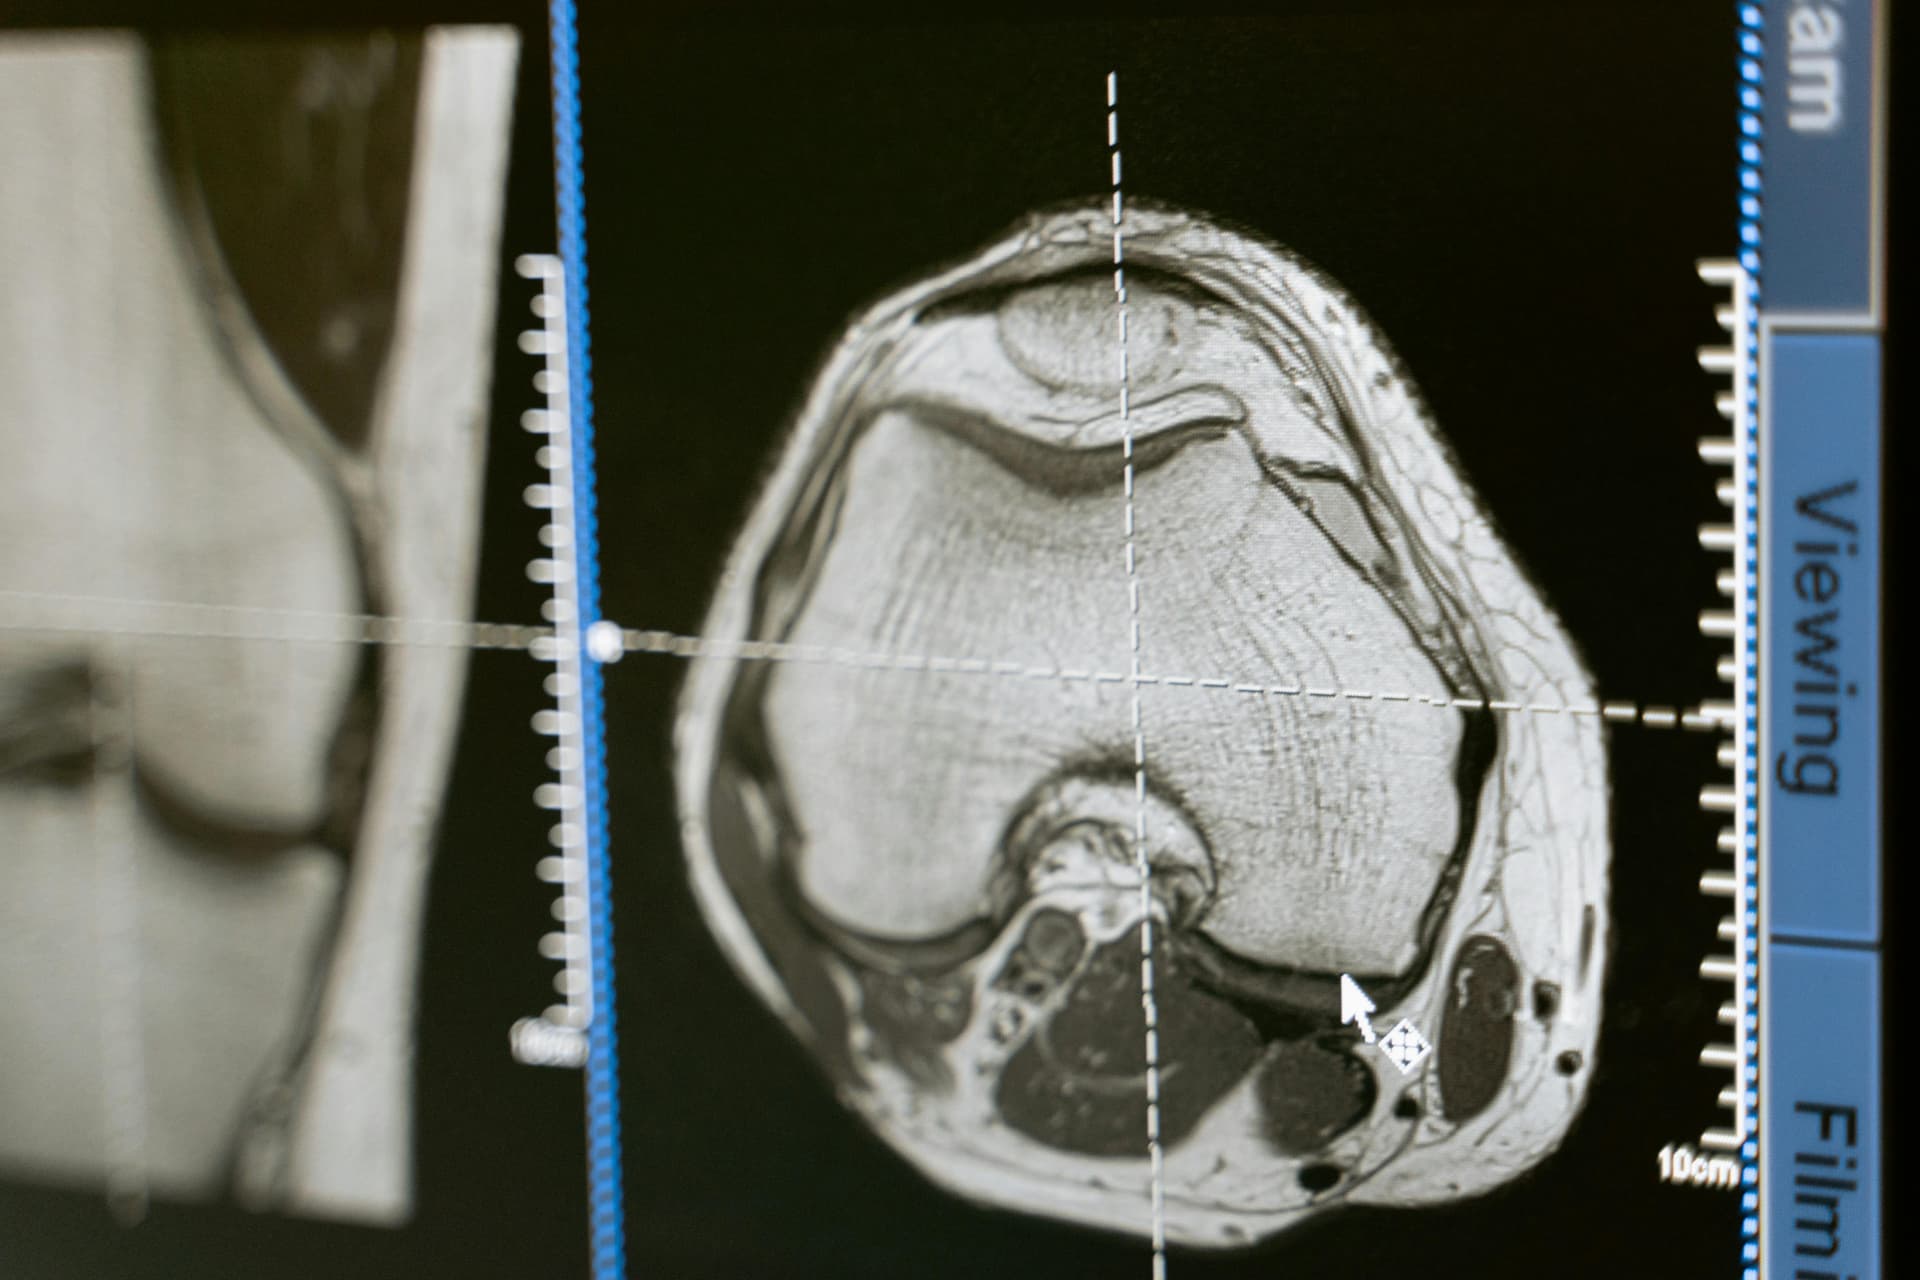

اختصاص دقيق في MSK

تُراجع جميع الحالات بواسطة اختصاصيي أشعة عضلية هيكلية يمارسون MSK بشكل مخصص.

رأي ثانٍ لتصوير العضلات والعظام. بالشكل الصحيح.

آراء ثانية مستقلة من اختصاصيي الأشعة العضلية الهيكلية تمنح وضوحًا في الحالات المعقدة.

يتطلب تصوير MSK خبرة ووضوحًا. نقدم آراء ثانية مستقلة بمستوى متميز مع تقارير مهيكلة وشارحة تقلل عدم اليقين وتدعم قرارات سريرية واثقة.